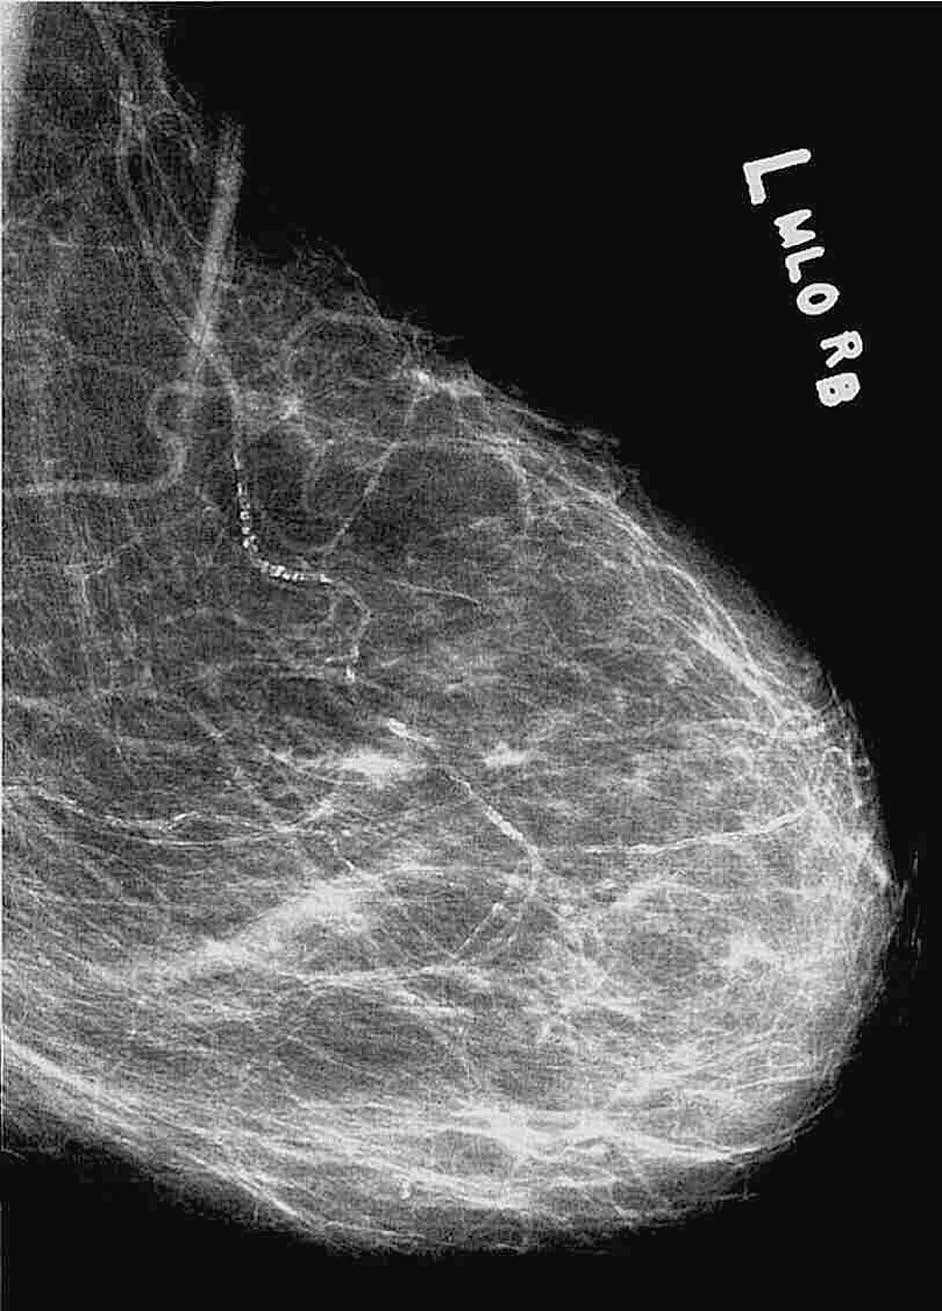

Cuando el radiólogo revisa las mamografías de screening o diagnóstico, incidentalmente detecta a veces calcificaciones no sospechosas de malignidad, de naturaleza y causas variadas3. Una de estas posibilidades es el hallazgo casual de calcificaciones arteriales en mamografía (CAM). Generalmente éstas son bilaterales y fácilmente reconocibles por su morfología mamográfica, por lo que no suelen causar confusión con las calcificaciones debidas a procesos malignos (fig. 1). Sólo muy raramente y en estadios precoces de la calcificación arterial estas imágenes pueden ser confundidas con las calcificaciones debidas a carcinoma in situ o invasivo.

Figura 1. Mamografía en proyección oblicua que muestra una calcificación en raíl, alargada y algo tortuosa, extendiéndose entre los cuadrantes internos y la región retroareolar. La imagen es característica de calcificación arterial mamográfica (CAM) Hamilton Depression Rating Scale; PHQ: Patient Health Questionnaire

Actualmente, la mamografía, si es realizada bajo parámetros adecuados de calidad en lo referente a la toma y procesado de la película, constituye probablemente la técnica radiográfica más sensible para la detección de calcificaciones de tamaño muy pequeño, tanto de tipo ductal como de carácter arterial (fig. 1).